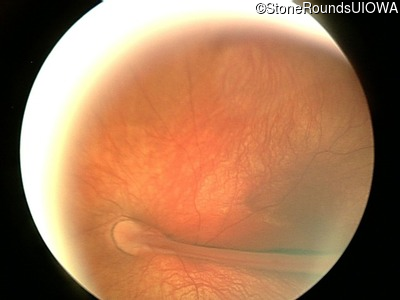

Fundus Photography - Right - 20/125

Exemplar